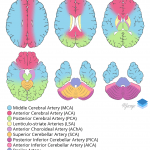

- Area of loss of gray-white differentiation in the left parietal lobe along the MCA/PCA watershed zone

- Acute left MCA/PCA and ACA/MCA watershed infarcts